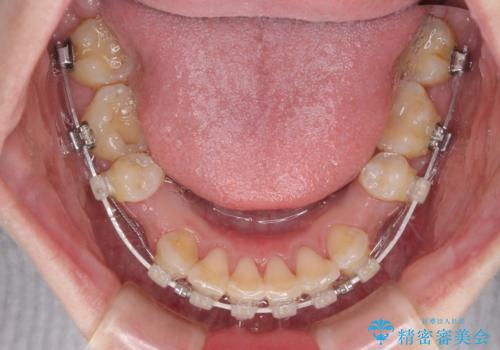

- 矯正装置

- 審美装置

上下前歯の距離が大きかったため、上下の歯が接触するまでに時間がかかりました。

それでも目安である2年半で終えることができ、患者様には大変満足していただけました。